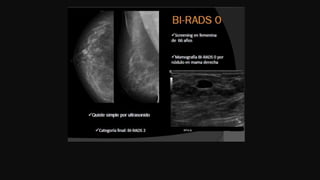

Reporte mamográfico Breast Imaging Report And Data System

Reporte mamográfico

Parénquima mamario

Breast Imaging Report And Data System

Tejido predominante: lipomatoso,escaso

tejido glandular

Tejido fibroglandular moderado.

Tejido fibroglandular abundante. (mamas

densas)

categorización

Recomendaciones.